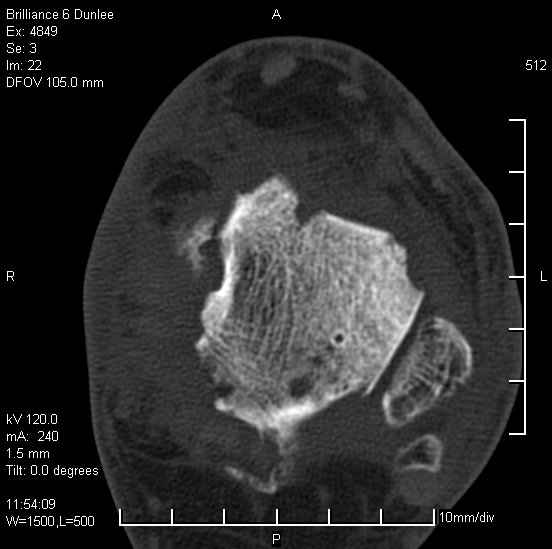

На лечении находится пациент 35 лет. Травма в сентябре 2008 г.- открытый вывих таранной кости

В день травмы ПХО, вправление вывиха, трансартикулярная фиксация. Рана зажила первично. С января нагрузка на конечность. С конца апреля- болевой синдром. На рентгенограммах и КТ признаки ас. некроза таранной кости, артроз подтаранного и голеностопного суставов.